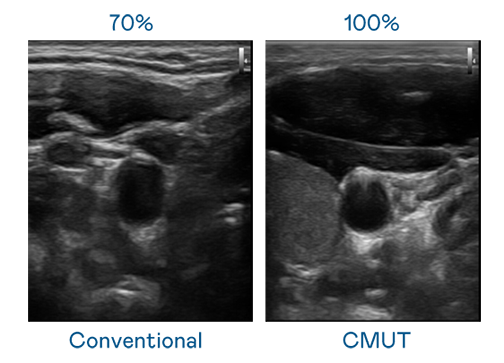

CMUT 技术是一种用电容式微机电元件来产生超音波讯号的技术。与传统 PZT 压电式技术相比,CMUT 频宽增加 30%,更宽频的超音波讯号让影像解析度大幅提升,是实现高影像品质医疗超音波扫描、促进精准医疗发展的关键技术。

超音波影像的解析度高低,首先取决于探头能发出的讯号频宽。金年会 CMUT 可提供高清晰的超音波讯号,提供高频宽、高灵敏度、影像纹理细节更高的超音波影像,协助医护人员缩短影像判读时间及利用精准的医疗影像进行诊断。